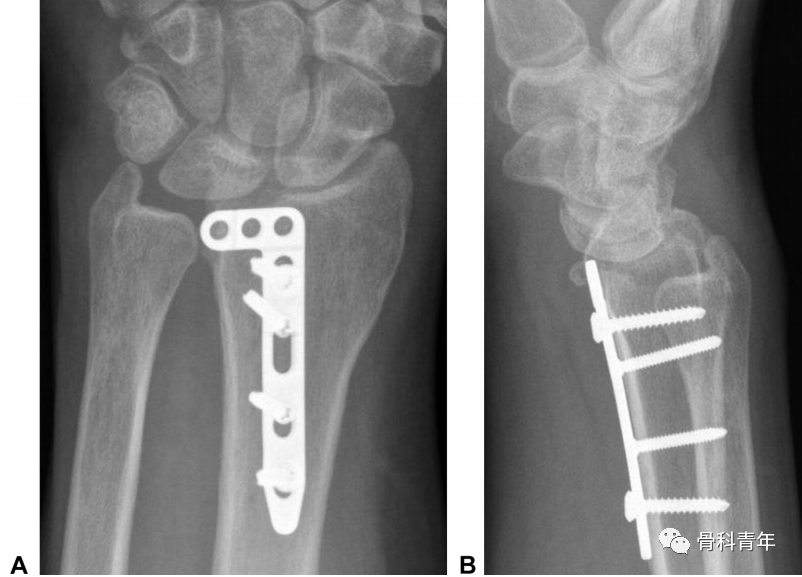

病例2:采用常规桡侧腕屈肌入路,掌侧钢板固定,术后发现腕关节前脱位,内固定失效。

对病例2,采用掌尺侧入路,柱钢板翻修后提示内固定位置良好。

鉴于常规桡骨远端骨折钢板在固定该骨块上存在以下缺陷:一是采用桡侧腕屈肌入路,显露欠佳,二是掌侧锁定板螺钉大,对小骨块固定不确切,并可能将螺钉置入骨块间隙导致骨块移位。因此学者建议采用2.0mm或2.4mm锁定钢板特异性固定中柱骨块。此外,除支撑钢板外,采用2枚螺钉固定骨块后,中和钢板保护螺钉,也是一种内固定的可选方案。